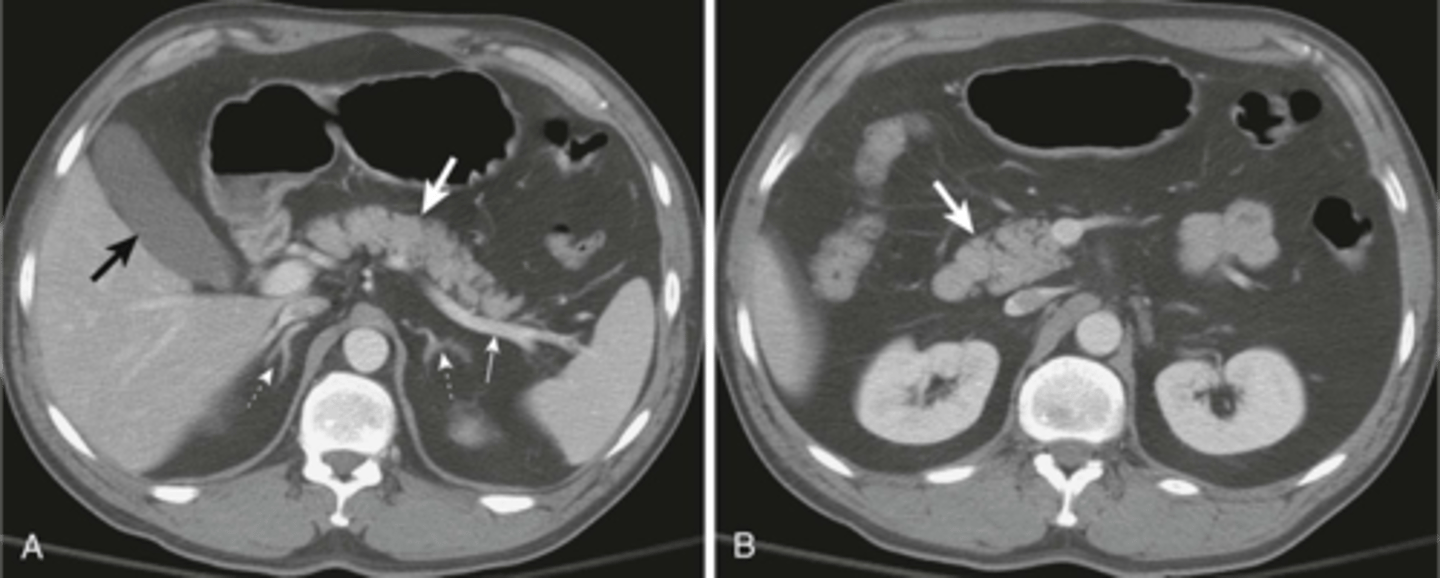

Abdominal aortic aneurysm on CT

Stent due to AAA